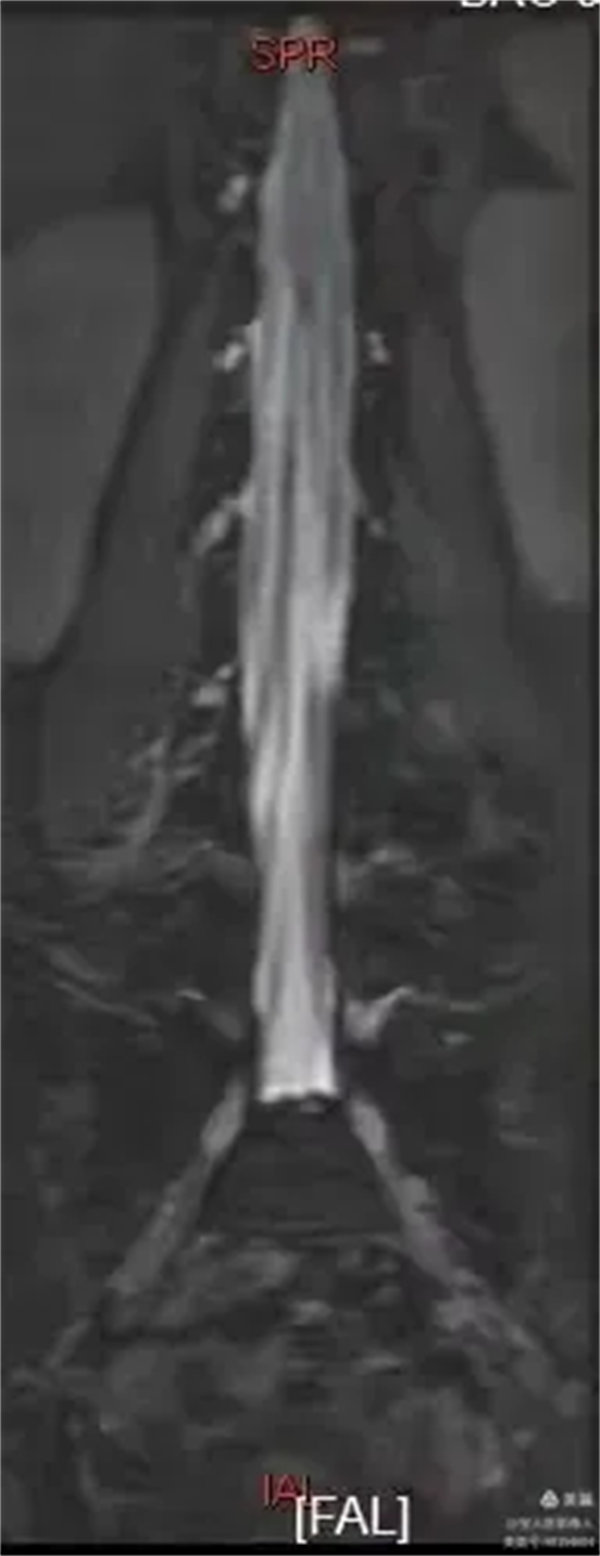

最大密度正面圖,顯示腰段硬膜囊內腦脊液(高信號),多條終絲(線狀稍低信號)縱向走行清晰。

最大密度正面圖,顯示腰段硬膜囊內腦脊液(高信號),多條終絲、腰神經及骶神經(線狀稍低信號)走行清晰。